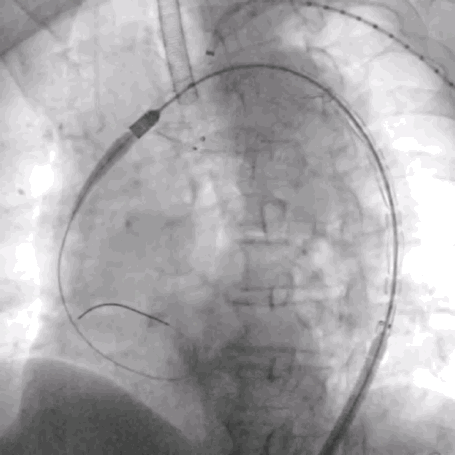

3. 沿左侧肱动脉Fustar内导入Fusmart可调弯导管及0.035"Terumo普通泥鳅导丝尾端,到达主动脉弓覆膜支架上方,调整角度,以尽量垂直角度透视下配合破膜,选入主体支架内,LSA导管内造影,多角度确认导丝头穿过主动脉支架覆膜。

泥鳅导丝怎么用符伟国/王利新教授团队:0.035"普通泥鳅导丝进行胸主动脉弓上分支原位开窗的病例分享_https://www.jmylbn.com_新闻资讯_第13张

LSA可调弯鞘内进可调弯导管

泥鳅导丝怎么用符伟国/王利新教授团队:0.035"普通泥鳅导丝进行胸主动脉弓上分支原位开窗的病例分享_https://www.jmylbn.com_新闻资讯_第14张

RAO方向确认导管

与大支架覆膜垂直

泥鳅导丝怎么用符伟国/王利新教授团队:0.035"普通泥鳅导丝进行胸主动脉弓上分支原位开窗的病例分享_https://www.jmylbn.com_新闻资讯_第15张

破膜成功

泥鳅导丝怎么用符伟国/王利新教授团队:0.035"普通泥鳅导丝进行胸主动脉弓上分支原位开窗的病例分享_https://www.jmylbn.com_新闻资讯_第16张

LSA导管内造影,确认破膜成功